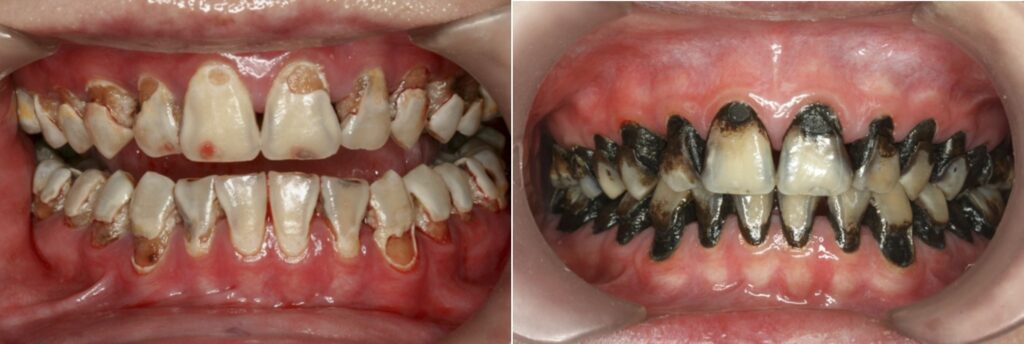

Nhược điểm cố hữu của SDF là các tổn thương sâu răng sẽ bị ố đen sau khi bôi. SDF ngăn chặn sự tiến triển của sâu răng bằng cách hình thành một lớp cứng, đen, không thấm nước trên bề mặt răng và có khả năng chống sâu răng.